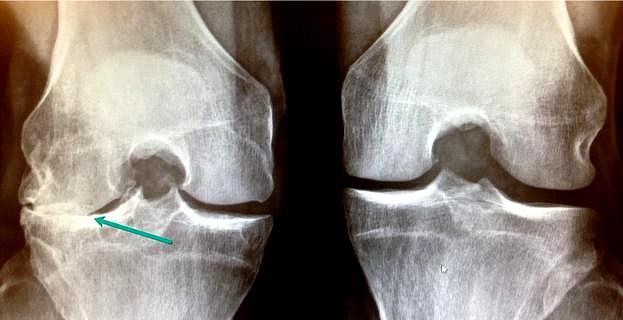

2014-03-26 陈月华 医师 我妈今年49了,左膝长了骨刺,拍了片子医生说